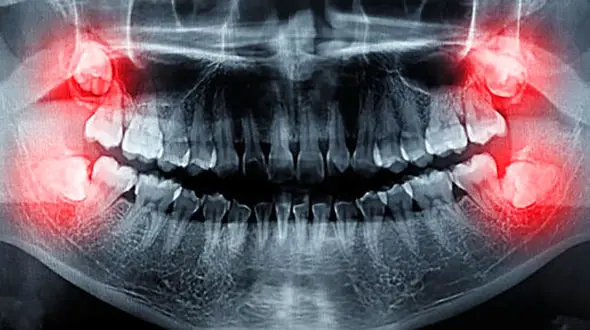

رکنا : دندان های عقل نهفته برای سلامت فرد خطرناک است.

سلامت رکنا : دندان عقل را باید به موقع کشید.